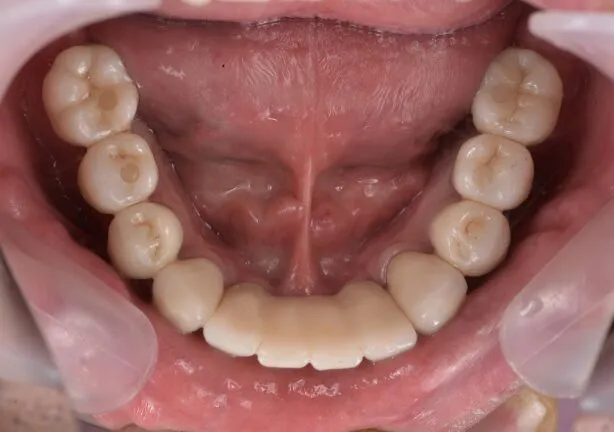

case2

Before

治療内容 | 口腔内診査〜カウンセリング 歯周初期治療 インプラント埋入 歯周外科治療 仮歯にてインプラントを含めた咬む位置の決定 最終的な被せ物(メタルセラミックスクラウン)の型取り〜装着 |

治療期間 | 2年半 |

治療回数 | 約80回 |

リスク | 手術、並びに治療における疼痛 連結をしている歯が二次的な虫歯、歯周病になりやすくなる 今後のメンテナンスが必須となる |

費用(税込) | 約¥4,950,000 |